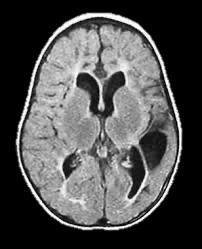

Germinal matrix-intraventricular haemorrhage (GMH-IVH)

Focal infarction

White matter injury

Global injury from hypoxic-ischaemic encephalopathy (HIE)